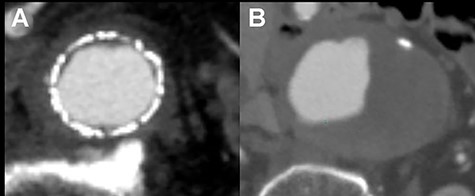

The patient recovered uneventfully, however, 1 year after open conversion, CT revealed a significant increase in the size of the unreplaced infrarenal aorta (Figs 3A, 4A and B). Reoperation was performed to treat the new aneurysm and on intraoperative findings, it was a true aneurysm. Abdominal aortic replacement was performed, however, infection of the vascular prosthesis occurred as a complication of this second open surgery. The infection was not controlled, and unfortunately, the patient died.

CT scan showing the significantly dilated infrarenal aorta, 1 year after open conversion (A, red arrow).

One year after open conversion, CT scan showing the significantly dilated infrarenal aorta (A) compared with the aorta before open repair (B).